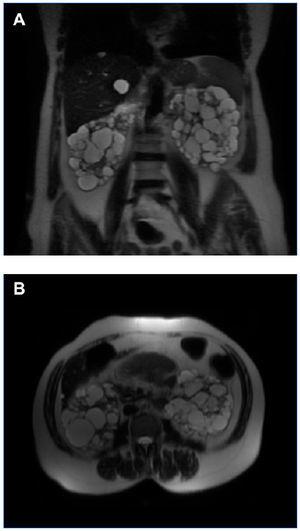

Figura 3. RM del caso 3 en la que se observan riñones que conservan su forma, con múltiples quistes pequeños (VRT = 603 ml). A) Corte coronal. B) Corte axial.